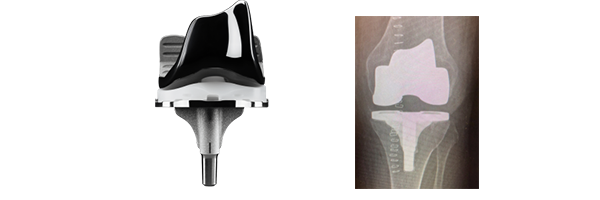

- La durée de vie de l’implant : taux de survie des grandes séries montrent 85-90% taux de survie à 20 ans de l’intervention.